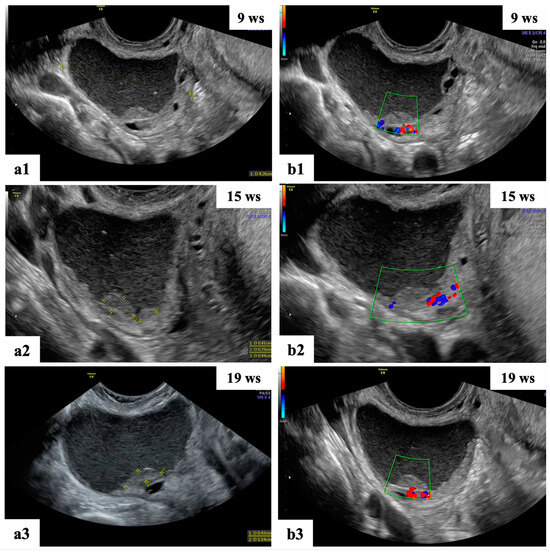

- Mascilini, F.; Moruzzi, C.; Giansiracusa, C.; Guastafierro, F.; Savelli, L.; De Meis, L.; Epstein, E.; Timor-Tritsch, I.E.; Mailath-Pokorny, M.; Ercoli, A.; et al. Imaging in gynecological disease. 10: Clinical and ultrasound characteristics of decidualized endometriomas surgically removed during pregnancy. Ultrasound Obstet. Gynecol. 2014, 44, 354–360. [Google Scholar] [CrossRef]

- Moro, F.; Mascilini, F.; Pasciuto, T.; Leombroni, M.; Li Destri, M.; De Blasis, I.; Garofalo, S.; Scambia, G.; Testa, A.C. Ultrasound features and clinical outcome of patients with malignant ovarian masses diagnosed during pregnancy: Experience of a gynecological oncology ultrasound center. Int. J. Gynecol. Cancer 2019, 29, 1182–1194. [Google Scholar] [CrossRef]

| Papillation flow Present Absent | 2/4 2/4 |